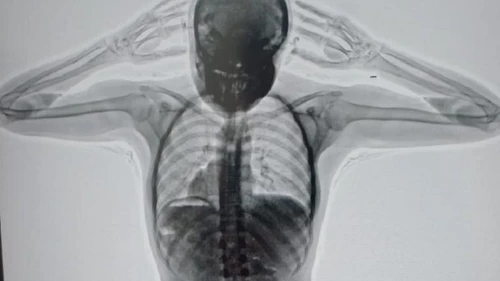

En ese momento, la chica, que días antes había cumplido 20 años, respondió de manera "dubitativa e incongruente" y los investigadores decidieron que pase por el Escaner de Rayos X.

Allí se descubrió que la joven había ingerido 78 cápsulas de 10 gramos de cocaína cada una y las llevaba dentro de su cuerpo. Quedó detenida y fue trasladada al Hospital Zonal General de Agudos Doctor Alberto Antranik Eurnekian.